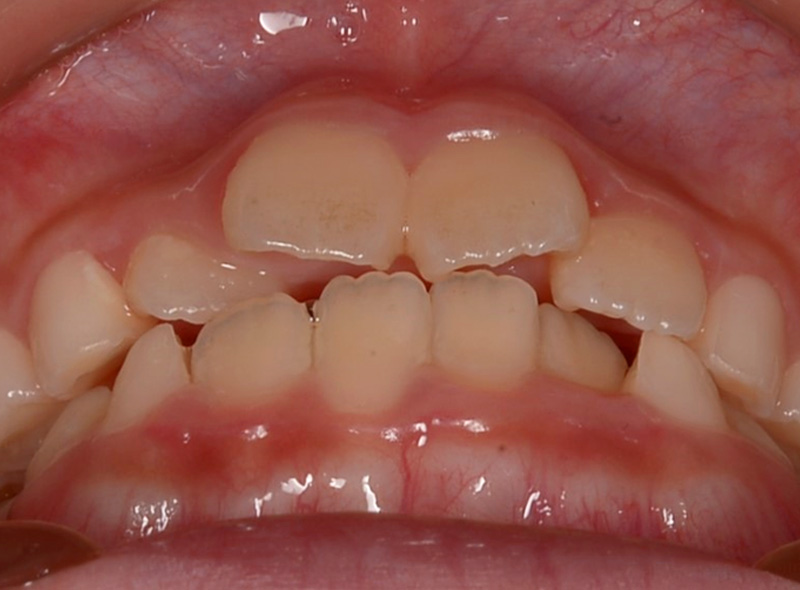

お子さんの前歯のガタガタが気になると来院されました。今の歯並びも気になるが、大人の歯に生え変わった後も綺麗な状態にしてあげたいという保護者のご希望があり、小児矯正から生え変わったあとの矯正までをしっかりとサポートする「通期矯正」を行いました。

口元比較

Before

After

口元比較 横側